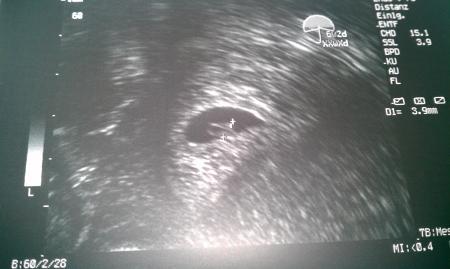

Der Krümel hat sich heute gezeigt. Er ist nun 3,9 mm groß und bubbert fleißig vor sich hin. Stück für Stück kann ich mir etwas mehr freuen.

Ja, den Dottersack konnte man gut erkennen und den minikleinen Embryo. Das schönste war es das Herz bubbern zu sehen. Damit habe ich gar nicht gerechnet. Mein Mann war auch sehr baff.

Ich hoffe ihr könnt den kleinen erkennen. Über dem Dottersack, bei dem Markierungspunkt.

Wow! Mann kann es so gut erkennen! :)